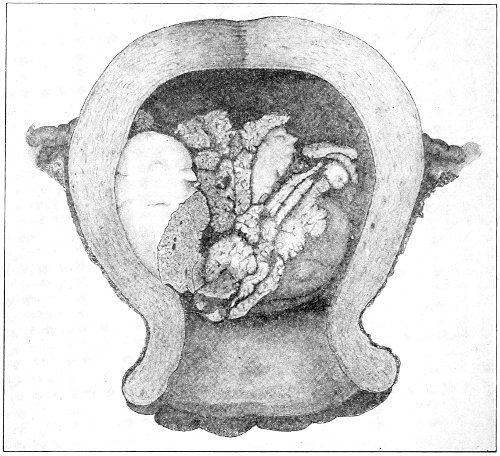

Fig. 18.—Cyst of the right vulvo-vaginal gland (Hirst).

Cysts of the gland may be unilocular if formed at the expense of a single lobule of the gland, or multilocular if several lobules enter into their formation. These cysts may attain the size of the fetal head (Fig. 18).

Cysts of the gland or of the duct are formed by retention of the cyst-contents. The retention is due to occlusion of the duct, usually the result of inflammation. In some cases the duct remains pervious, and the retention is due to the altered character of the secretion of the gland, which becomes too viscous to pass, except under unusual pressure, along the duct.

These cysts contain clear yellow or chocolate-colored 42 fluid. The diagnosis of cyst of the vulvo-vaginal gland is usually not difficult. If we are in doubt in regard to the fluid character of the tumor, this may be determined with the exploring-needle.

Inguinal hernia, hydrocele of the canal of Nuck, cysts of the round ligament, and sacculated cysts of old hernial sacs may be mistaken for cysts of the vulvo-vaginal glands. In such cases, however, the tumor lies more in the upper and outer part of the labium majus, and extends to, and may be connected with, the external inguinal ring.

Cysts of the vulvo-vaginal glands should be treated by free incision and packing, or by extirpation. If the sac is emptied by the aspirator or by a small incision, it will refill. The best method is to extirpate the cyst. In case there has been no inflammatory action binding the cyst to surrounding structures, extirpation without rupture is easy. If rupture occurs, the cyst-wall may be dissected off with the knife or removed with the curved scissors. The wound may be immediately closed with deep and superficial sutures.